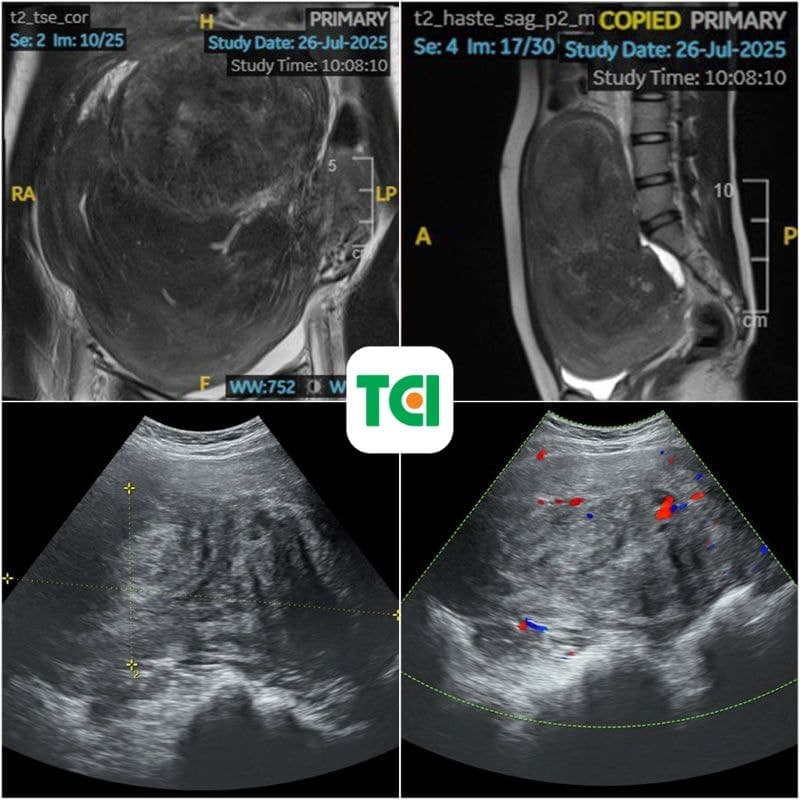

Kết quả thăm khám lâm sàng và cận lâm sàng khiến cả người bệnh lẫn bác sĩ đều bất ngờ: khối u xơ đã phát triển tới kích thước 250 x 200mm, tương đương thai 7 tháng, trọng lượng lên đến 2,1kg.

Hình ảnh MRI cho thấy khối u chiếm gần trọn ổ bụng, chèn ép tử cung và các quai ruột, một phần dính vào đại tràng và thành bụng. “Đây là kích thước rất lớn, đặc biệt hiếm gặp ở phụ nữ trẻ chưa từng sinh con,” bác sĩ Nguyễn Văn Hà – Trưởng khoa Phụ sản, Bệnh viện ĐKQT Thu Cúc TCI cho biết.